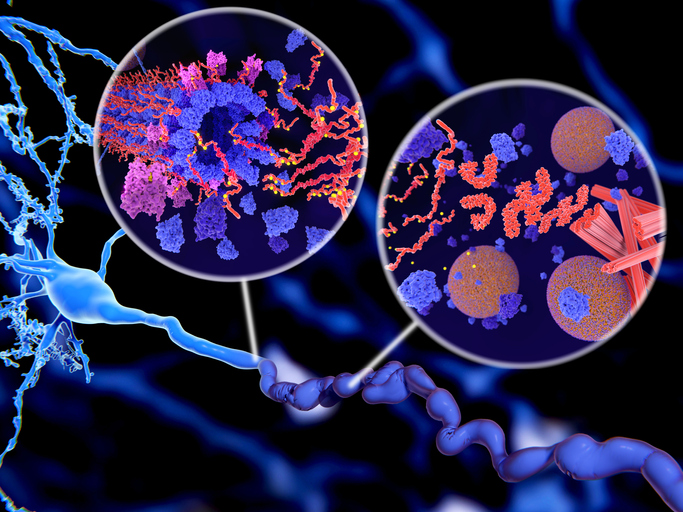

Στο Αλτσχάιμερ, τα νευροϊνιδιακά νήματα είναι φτιαγμένα από μια πρωτεΐνη γνωστή ως tau (Τ).

Τα κύτταρα του εγκεφάλου περιέχουν ένα δίκτυο από σωληνάρια που είναι σαν δρόμοι για μόρια τροφίμων μεταξύ άλλων.

Συνήθως, η Τ-πρωτεΐνη φροντίζει ώστε αυτά τα σωληνάρια να είναι ίσια, επιτρέποντας στα μόρια να διέλθουν ελεύθερα μέσα τους.

Αλλά στο Αλτσχάιμερ, η πρωτεΐνη καταλήγει σε μπερδεμένες πλάκες ή νήματα, διαλύοντας τα σωληνάρια κι εμποδίζοντας τα θρεπτικά συστατικά να φτάσουν το νευρικό κύτταρο, το οποίο και πεθαίνει.

Η παθολογική φωσφορυλίωση (κίτρινο) της Τ-πρωτεΐνης (κόκκινο-πορτοκαλί) οδηγεί σε αποσύνθεση των μικροσωληνίσκων και η προκύπτουσα συσσωμάτωση σε νευροϊνιδικά νήματα (πορτοκαλί) σε έναν νευρώνα. Η μεταφορά των συναπτικών κυστιδίων (σφαίρες) διακόπτεται.